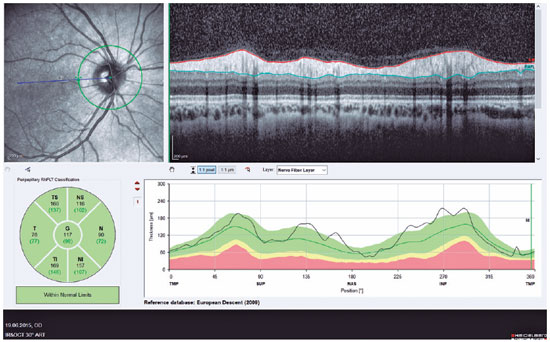

RNFL thickness, central macular thickness (CMT), and central subfoveal choroidal thickness (CSCT) were measured using the Spectralis OCT. The procedure used to obtain enhanced depth imaging (EDI)-OCT was described previously(11). Briefly, CSCT was measured using spectral-domain OCT (Spectralis) with EDI modality. CSCT was defined as the vertical distance from the hyper-reflective line of Bruch’s membrane to that of the inner surface of the sclera. A single experienced technician imaged all of the study subjects, and two masked clinicians (IY and NB) without any knowledge of the subject matter independently measured CSCT and presented theme an values. Measurements for which differences >10% were recorded between the interpreters were excluded. Thickness parameters of the peripapillary RNFL were automatically calculated using spectral-domain (SD)-OCT and divided into regions including average RNFL (G) thickness (360°), temporal (T) quadrant thickness (90°), temporal superior (Ts) quadrant thickness (45°), nasal superior (Ns) quadrant thickness (45°), nasal (N) quadrant thickness (90°), nasal inferior (Ni) quadrant thickness (45°), and temporal inferior (Ti) quadrant thickness (45°). SD-OCT CMT, CSCT, and peripapillary RNFL thickness imaging of a normal eye are shown in figures 1 and 2, respectively.